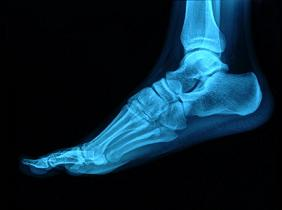

Talalgia por fascitis plantar y espolón calcáneo

La talalgia es el nombre que se le da al dolor en el talón. Este tipo de patología es muy frecuente, sobre todo en deportistas debido a que el talón…